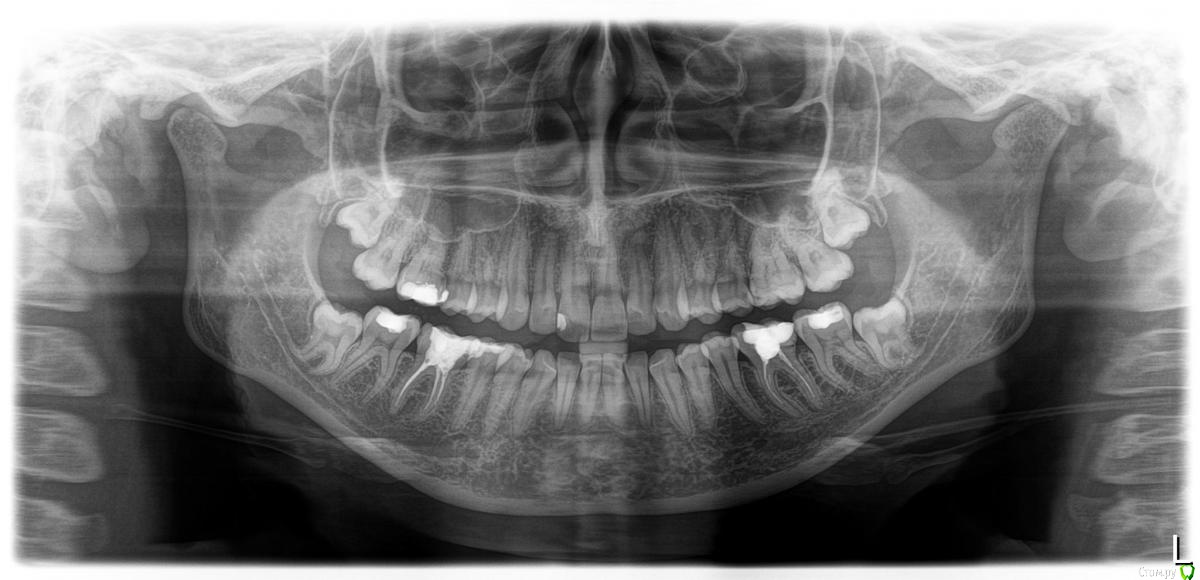

София21 Опубликовано 14 января, 2020 Поделиться Опубликовано 14 января, 2020 (изменено) Здраствуйте. Пишу потому что не могу уже терпеть эту боль. 19 декабря удалила верхнюю 8ку, а 26 декабря нижнюю 8ку. И все это время на обезбаливающих сижу. Потому что без них на стену лезть охота. После удаления верхнего зуба швы не накладивали, и сгусток кровяной там не образовался, 2 раза делали чистку (закладывали лекарсто, на ренгене его видно). Когда нижний удаляли, то зашывали кетгутом дыру. Приписали антибиотики сначала одни, потом другой через неделю. Аугментин а потом Далацин Ц. Болит вся правая половина и все зубы. (и передный, который депульпирован). Когда эти муки прекрататся? Есть два снимка до удаления и после (сделан 12 января). Удаляли зубы долотом, и сверлили очень много бор машиной по кругу . Еще 2 надо удалить но уже боюсь.(((( Изменено 14 января, 2020 пользователем София21 Ссылка на комментарий

Irouil Опубликовано 15 января, 2020 Поделиться Опубликовано 15 января, 2020 два снимка више есть, до удаления и после Снимок во рту - это фотография. Неплохо бы проверить наличие пульпита на любом из зубов с правой стороны полости рта Можете попробовать сходить на консультацию ещё к кому-нибудь Ссылка на комментарий